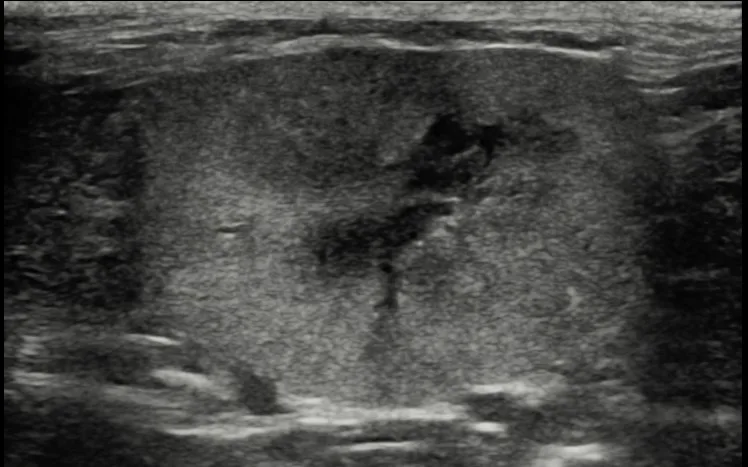

Hematology profile is unremarkable, except for hematocrit toward the lower end of the reference interval (27%; reference interval, 24%-45%). Urinalysis reveals inactive sediment with a urine specific gravity of 1.014 and urine protein:creatinine ratio of 1.2 (reference interval, 0-0.4). Abdominal ultrasonography confirms both kidneys are small and diffusely hyperechoic with loss of corticomedullary definition, suggestive of chronic nephropathy (Figure 2).

FIGURE 2 Ultrasound image of a kidney that is diffusely hyperechoic with loss of corticomedullary definition in a cat with CKD